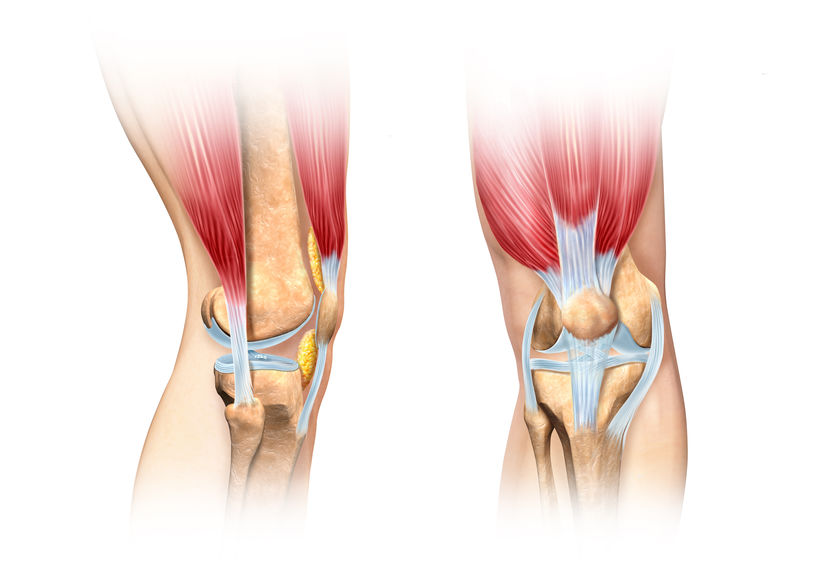

Ścięgna, więzadła i mięśnie są strukturami kończyny górnej i dolnej, które warunkują prawidłową motorykę (czynność) narządu ruchu i ręki. Uszkodzenie ścięgien i więzadeł związane jest z dysfunkcją narządu ruchu oraz najczęściej ograniczeniem ruchomości, bólem, obrzękiem, zasinieniem, krwiakiem. Ścięgna i więzadła zbudowane są z tkanki łącznej, której głównym składnikiem są włókna kolagenowe, natomiast mięśnie zbudowane są z włókien mięśniowych gładkich lub poprzecznie prążkowanych.

Uszkodzenie ścięgien i więzadeł następuje najczęściej w wyniku oddziaływania gwałtownej siły przekraczającej wytrzymałość mechaniczną tych struktur lub poprzez stałe mikrourazy, które powodują stopniowe uszkadzanie włókien, krwiaki i następnie powstanie wewnątrz ścięgien, mięśni lub więzadeł blizn, zwłóknień i zwapnień. Uszkodzeniom wysokoenergetycznym może towarzyszyć złamanie kości, zwichnięcie w stawie lub oba jednocześnie. Wystąpieniu uszkodzenia towarzyszy ból ostry lub przewlekły.